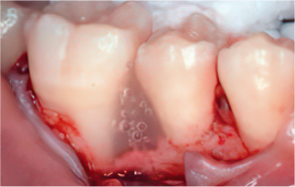

STEP 04

Emdogain application

-

STEP 05

Cleansing